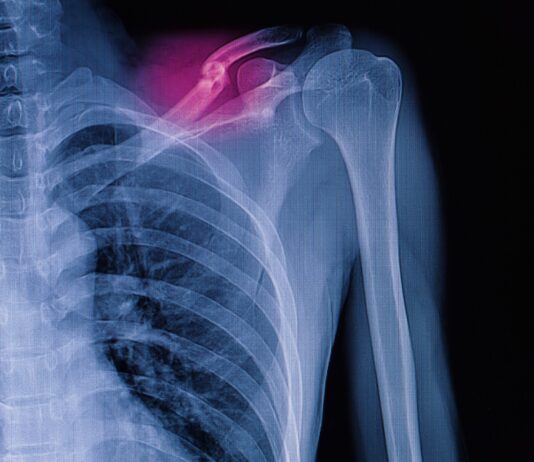

Frattura di caviglia: benefici della crioterapia di terza generazione preoperatoria

Abbastanza frequente tanto tra gli anziani, quanto tra i giovani, le fratture di caviglia vengono spesso trattate con...